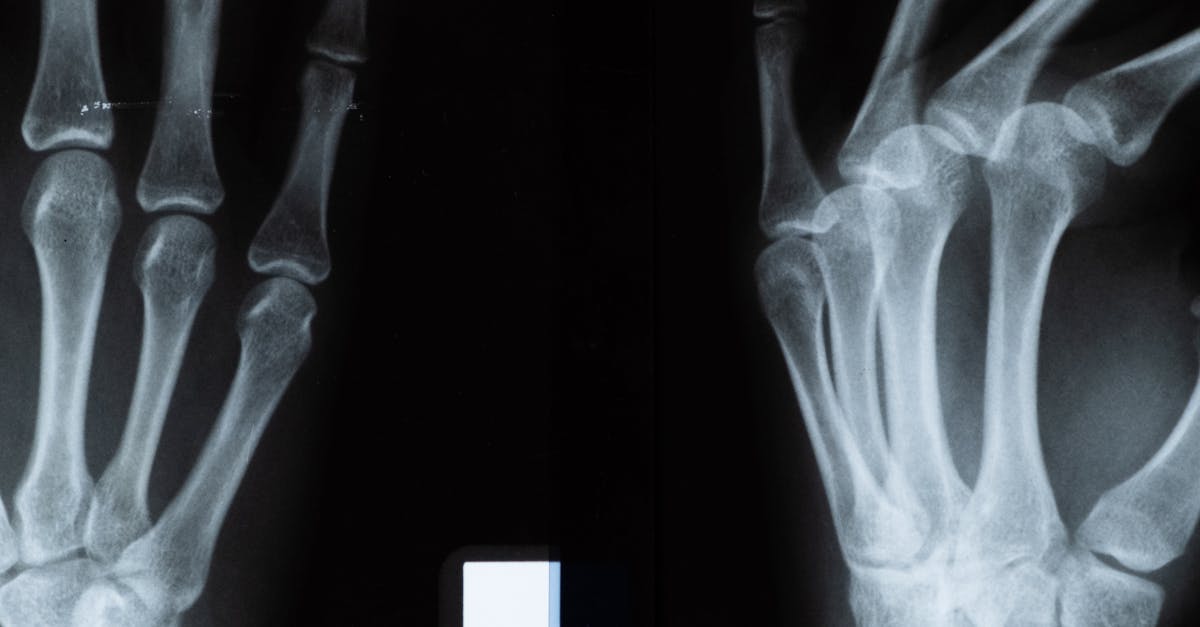

Medical imaging plays a crucial role in enhancing patient care by providing valuable insights into the body's internal structures. Through techniques such as X-rays, CT scans, and MRIs, healthcare providers can accurately diagnose various medical conditions, leading to timely and appropriate treatment interventions. For instance, medical imaging enables physicians to identify fractures, tumors, and other abnormalities that may not be visible through physical examination alone.